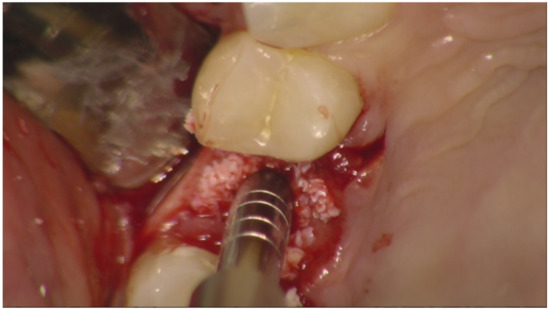

Implant Placement Following Crestal Sinus Lift with Sequential Drills and Osteotomes: Five Years after Final Loading Results from a Retrospective Study

2. Materials and Methods